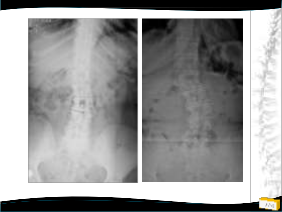

2009 2011

• Radyolojik değerlendirme

– Uzun kaset (26’’) filmler

• Ayakta ve yatarak

– Eğrilik (Cobb) ve fleksibite

ölçümü

– Koronal ve sagittal denge

– Spinopelvik parametreler

• PI-LL